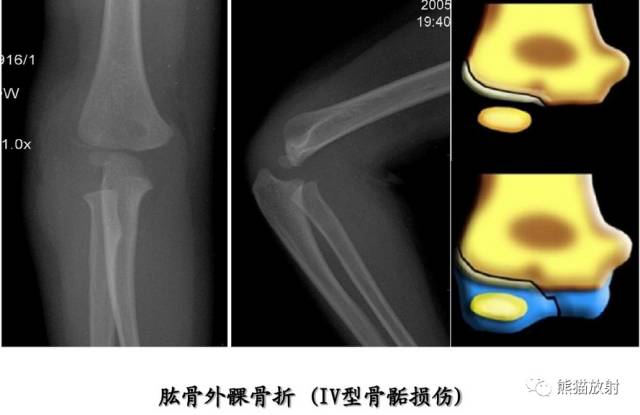

Salter-Harris IV型:骨折累及骺板、干骺端及骨骺,属于关节内骨折。

第四型(Ⅳ型) 骨骺和干骺端骨折。该型也较多见,仅次于第二型,占30.2%;骨折线呈斜形贯穿骨骺、骺板及干骺端,由于骨折线同过生长板全层,所以容易引起生长发育障碍和关节畸形,多见者为鱼尾状畸形。此型多见于10岁以下小儿的肱骨外髁及年龄较大儿童的胫骨远端,此型必须切开复位及内固定。